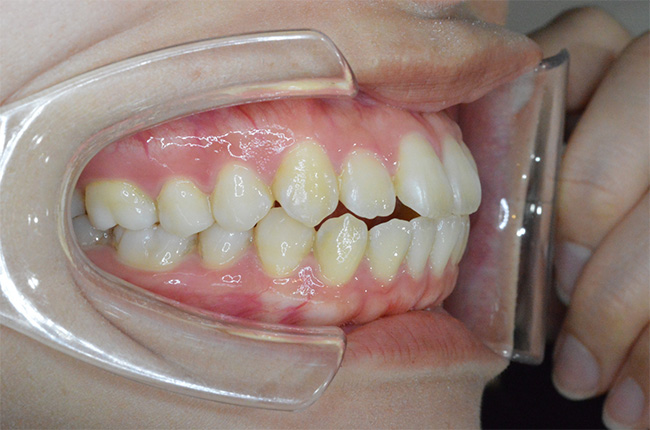

治療開始時